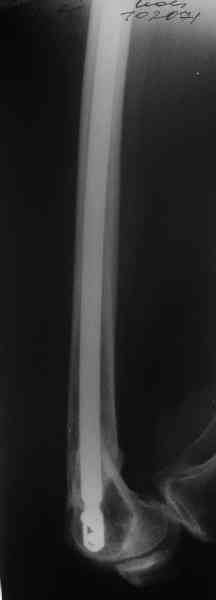

I> Насчет снимка Вами представленного - смотрится оч красиво, еще бы на

I> функцию узнать...

В приложении функциональные снимки в 3 мес. и в 1 год.